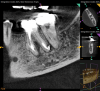

Just as systemic conditions and patient habits impact outcomes after NSRCT, the local dental environment and dental disease states also impact outcomes (Figure 1 through Figure 5). In the Toronto study evaluating 4- to 6-year outcomes following NSRCT, the presence of a periapical radiolucency emerged as a key prognostic factor, substantially reducing the success rate by a factor of four.12 Single-rooted teeth experienced better outcomes compared to multirooted teeth in the presence of periapical lesions.1 Teeth diagnosed preoperatively with irreversible pulpitis or necrosis, in the absence of AP, showed a more favorable prognosis compared to those with preoperative AP.2

Fig 1. NSRCT can have high success, even with risk factors like periapical pathology associated, as depicted in this case presentation. Fig 1: Preoperative periapical radiograph showing AP. Fig 2: Preoperative CBCT. Fig 3: Immediate postoperative periapical radiograph. Fig 4: Three-month follow-up CBCT showing reduction of periapical radiolucency. Fig 5: One-year follow-up periapical radiograph showing resolution of periapical radiolucency.

Fig 2. NSRCT can have high success, even with risk factors like periapical pathology associated, as depicted in this case presentation. Fig 1: Preoperative periapical radiograph showing AP. Fig 2: Preoperative CBCT. Fig 3: Immediate postoperative periapical radiograph. Fig 4: Three-month follow-up CBCT showing reduction of periapical radiolucency. Fig 5: One-year follow-up periapical radiograph showing resolution of periapical radiolucency.

Figure 2

Fig 1 through Fig 5. NSRCT can have high success, even with risk factors like periapical pathology associated, as depicted in this case presentation. Fig 1: Preoperative periapical radiograph showing AP. Fig 2: Preoperative CBCT. Fig 3: Immediate postoperative periapical radiograph. Fig 4: Three-month follow-up CBCT showing reduction of periapical radiolucency. Fig 5: One-year follow-up periapical radiograph showing resolution of periapical radiolucency.